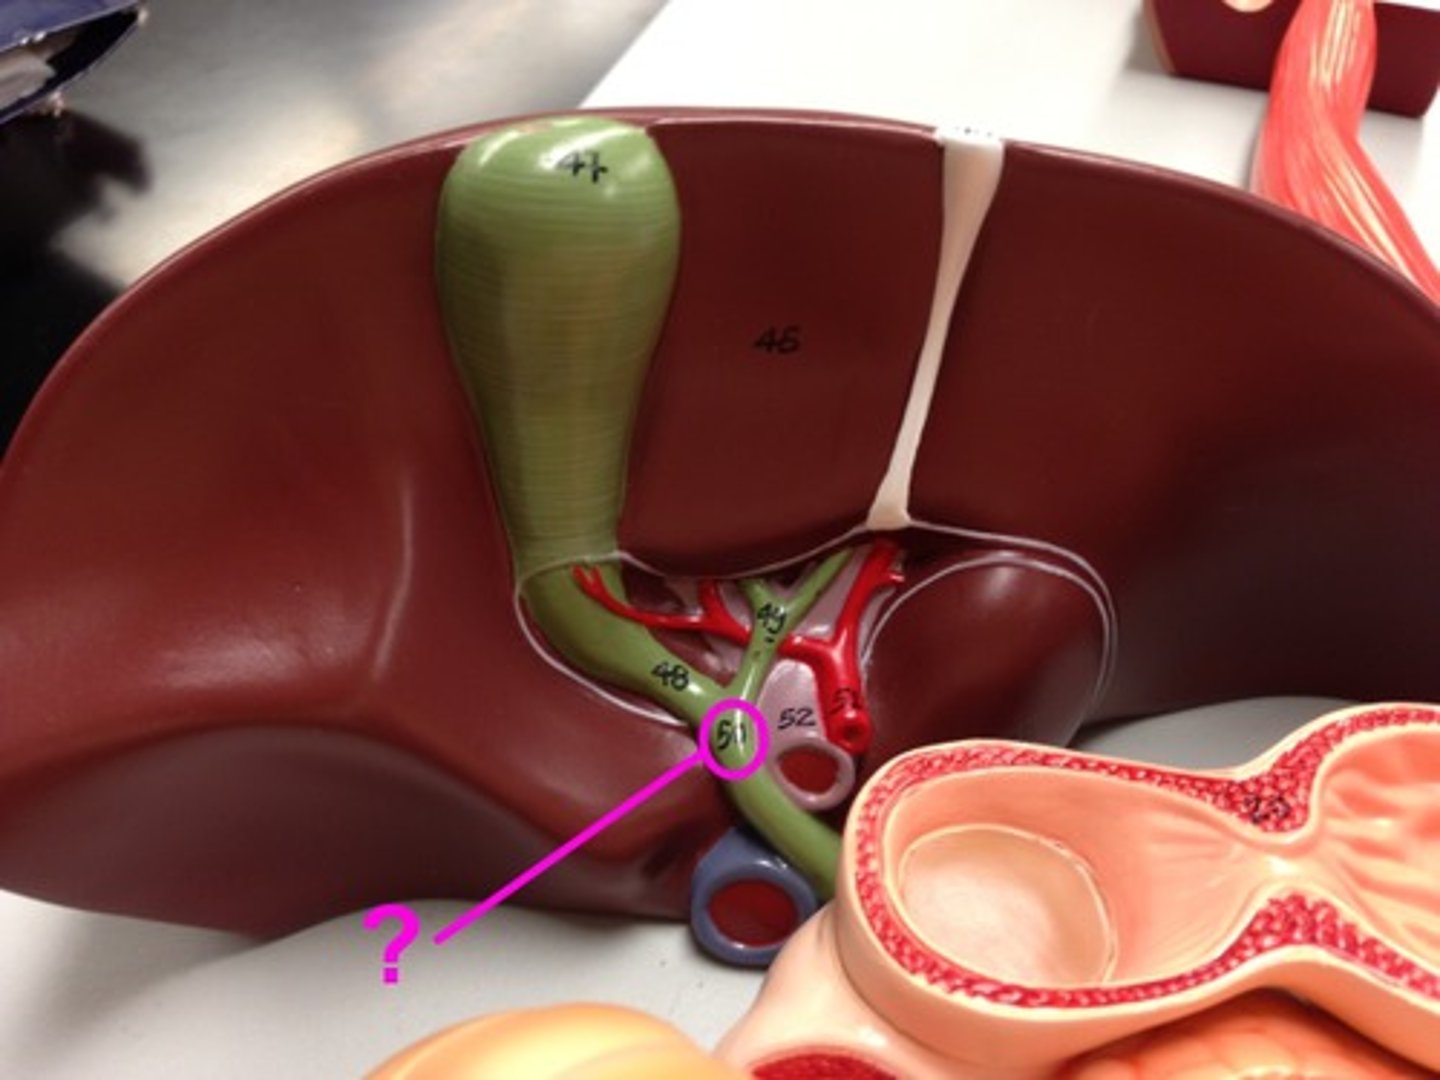

cystic duct

common hepatic duct

Gallbladder

portal vein

pancreatic duct

common bile duct

hepatopancreatic sphicter / duodenal papilla